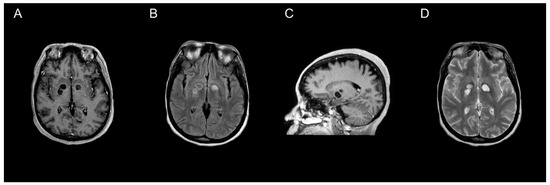

All 47 individual patients included in our review underwent neuroimaging, of which MRI was utilized more often than CT (66% vs. 34%, respectively). Though CTs are often preferentially performed due to availability and timeliness [61], previous data suggest increased sensitivity for detecting cryptococcoma lesions using gadolinium-enhanced MRI compared to standard MRI or CT [10,54,61]. MRI findings vary, ranging from hyper-intense on T2-weighted images, to non-enhancing on postcontrast T1-weighted images (Figure 1). Due to the rarity of cerebral cryptococcomas and challenges associated with diagnosis, it is common for them to be mistaken for neoplasms, as well as pyogenic or tubercular abscesses, prior to surgery [52]. Less often, cerebral cryptococcomas have been misdiagnosed as neurocysticercosis [39], or even a tumefactive demyelinating lesion, a rare focal demyelinating disease [62]. Cryptococcomas are sometimes confused in neuroimaging with dilated perivascular spaces (Virchow–Robin spaces) that coalesce to form gelatinous pseudocysts [63]. However, cryptococcomas resulting from invasion of Cryptococcus spp. into the brain parenchyma may develop in a variety of locations throughout the brain [10,11,52]. The frontal and parietal lobes (21% and 19%, respectively), as well as the basal ganglia (21%) were most often involved, whereas the thalamus (5%) or the pons (2%) were rarely involved among the 47 individual patients included in our analysis. The median number of lesions identified was one, but ranged from one to three among reports that provided specified details. Forty-seven percent of patients were noted to have more than one or multiple lesions throughout the brain parenchyma, which was more common amongst patients with C. gattii (Table 2). Characteristics of the lesions were not universally reported, but the size of the cryptococcomas varied substantially from less than 1 cm to 5 or 6 cm. C. neoformans was identified more often among cases where measurements were provided [23,24,34,44,50]. Perilesional edema and hydrocephalus were slightly more common among patients with C. neoformans than those with C. gattii (Table 2). Intracranial imaging is a valuable tool to determine the extent of disease severity in patients with disseminated cryptococcosis, but is insufficient to establish a diagnosis of cerebral cryptococcoma.

Figure 1. MRI characterization of cryptococcomas. MRI of the brain showing a nonenhancing cryptococcoma (axial plane T1-weighted post contrast (A), axial plane T2-FLAIR (B), post-contrast parasagittal (C), and axial plane T2-weighted (D)).